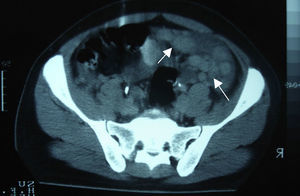

Clinical caseA 24-year-old male patient, with no history of surgeries, trauma, autoimmune diseases or medication intake. He presented symptoms 4 weeks before his admission, including sudden colic, sporadic, 10-minute long abdominal pain in the right hypochondrium, accompanied by early satiety, hyporexia and involuntary loss of 10kg of weight in the last 3 months. The patient denied having fever, asthenia, adynamia, as well as other relevant history. On admission, he was found to be haemodynamically stable, without fever and without relevant pathological data. He presented a soft, depressible, globus abdomen, with diminished peristalsis, without pain on palpation and without visceromegaly. Alpha-fetoprotein of 4.28IU/ml, CA-125 of 110IU/ml and lactic dehydrogenase of 1025IU/l were observed. The abdominal computed tomography showed the presence of multiple nodular-to-ovoid lesions in the abdominopelvic cavity, of increased density, which had no apparent organic origin, the largest of which was 6cm×4cm, and were well defined. These findings suggested peritoneal carcinomatosis with metastatic retroperitoneal adenopathies (Figs. 1 and 2).

Among the studies conducted for its diagnosis, the abdominopelvic computed tomography generally involves one or multiple tumours of lobulated and well-defined borders, with hyperdense and heterogeneous soft tissue, with hypodensity areas related to necrosis and haemorrhage foci, located in the intraperitoneal region, without apparent abdominal organic origin. About 50% may present adenomegalies and 20% may present calcifications. Bellah et al.15 reported that lesions were located in the vesical rectum and/or urinary rectum in 82% of the cases.3–5,15